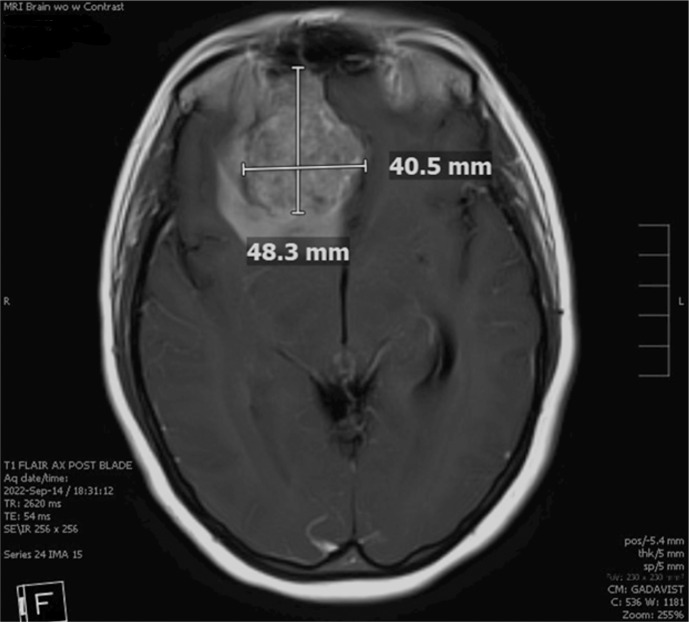

Case presentation: We report a case of a 48-year-old female patient who presented with headache, nausea, and vomiting. Initial imaging revealed a 6.4 × 4.5 cm extra-axial mass in the right frontal region, originating from the superior right nasal cavity. She underwent surgical resection of the tumor and was found to have SNTCS. She received concurrent chemoradiotherapy. Next-generation sequencing showed mutations in the PTEN, SMARCA4, and CCND1 genes. Six months after completion of treatment, she experienced an aggressive leptomeningeal recurrence of her disease. To our knowledge, our case represents the first SNTCS case with a documented PTEN mutation. In the absence of evidence-based guidelines due to the rarity of this diagnosis, we have reviewed over 50 cases reported in the literature.